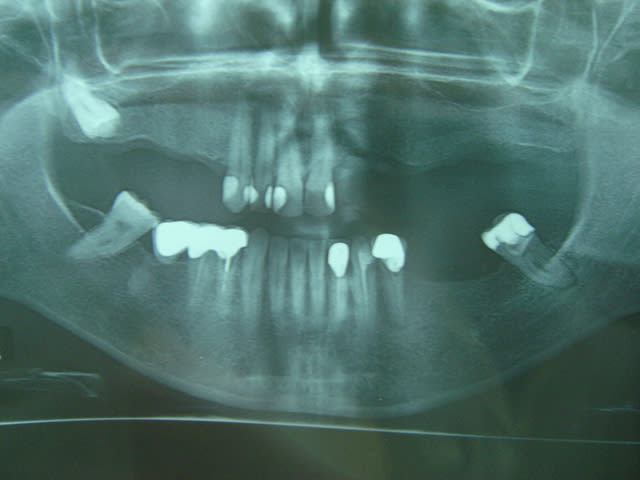

je pense que vous êtes allez loin du sujet d'implantologie pour vous remettre sur rails: qu'en pensez vous de de ce cas?surtout secteur 2.

sur le pano : pas de problème particulier (même si la crête semble fine) mais pas assez de données.

Merci pxav,en réalité c'est une patiente d'une collégue qui demande un avis, et c'est l'image de l'os au niveau 22 ,23 qui m'inquiéte,

c'est l'image de l'os au niveau 22 ,23 qui m'inquiéte,

même chose on a une vue plate.

qu'est ce qui te gène?le manque de hauteur?

c'est vrai que l'on a une impression de tissus osseux "flottant" au dessus de la crête.

Y a t-il eu déjà une greffe ? un comblement type xenogreffe ? une racine comme sous le cantilever en bas....

y'a t il un scan ou au moins des rétro alvéolaire pour préciser ?